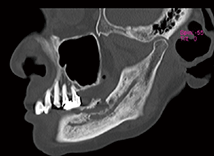

図❷ 初診時のCT画像(矢状断)

画像検査: パノラマX線写真にて、抜歯窩に腐骨様不透過像の分離を認める(図❶)。CTにて、抜歯窩相当部位に炎症性透過像と腐骨様不透過像の分離を認める(図❷)。